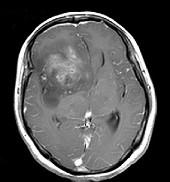

问题 女,32岁,头痛1年,复视4个月,请根据所提供图像,选择最可能的诊断()

选项 A.(右额颞)胶质母细胞瘤 B.(右额颞)多形性黄色星形细胞瘤 C.(右额颞)混合性胶质瘤(星形细胞和少突细胞) D.(右额颞)毛细胞型星形细胞瘤 E.(右额颞)室管膜下巨细胞星形细胞瘤

答案 C